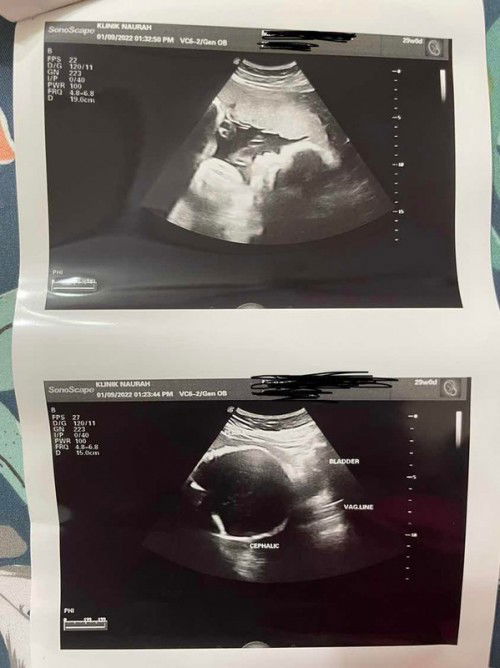

Hi ibu2.. i nak share pengalaman.. skrg i dh 29w.. i checkup dekat kk and before this dr sahkan i plecenta previa ( PP ) and i dpt tahu masa 20w mcm tu then i terus pergi buat details scan dekat luar masa 24w mcm tu x silap.. and masa i buat details scan tu dr ckp i bukan PP and with no stage.. okay then now korang tau i 29w ni i kena check up semula kt kk.. i tekejut now dr kk ckp i PP stage 4..means uri tutup jalan sepenuhnya..i tak puas hati dan terus pergi buat scan dekat luar skali lagi dan dr kt klinik luar ckp i masih bukan PP dan ini bukti yang i share.. btw i dah kena refer to hospital kerajaan untuk check dgn dr pakar btul ke i PP.. please doakan i harap kk silap and i xperlu czer or tahan ward dri 29w smpai bersalin.. hmm i nak bersalin normal.. skrg i tnggu jelah dr pakar ckp apa.. i harap dr kk tu silap.. sbb i yakin i bukan pp.. i xtau la dr kk mgkin silap position masa scan or mesin dorang dah patut kne tukar sbb kabur and x jelas masa scan apa pun pandangan dr untuk bidang ni akan berbeza pandangan dengan kepakaran masing2.. so i cuma harapkan scan untuk 6/9 sahkan i bukan pp π© doakan i ya mummy2..